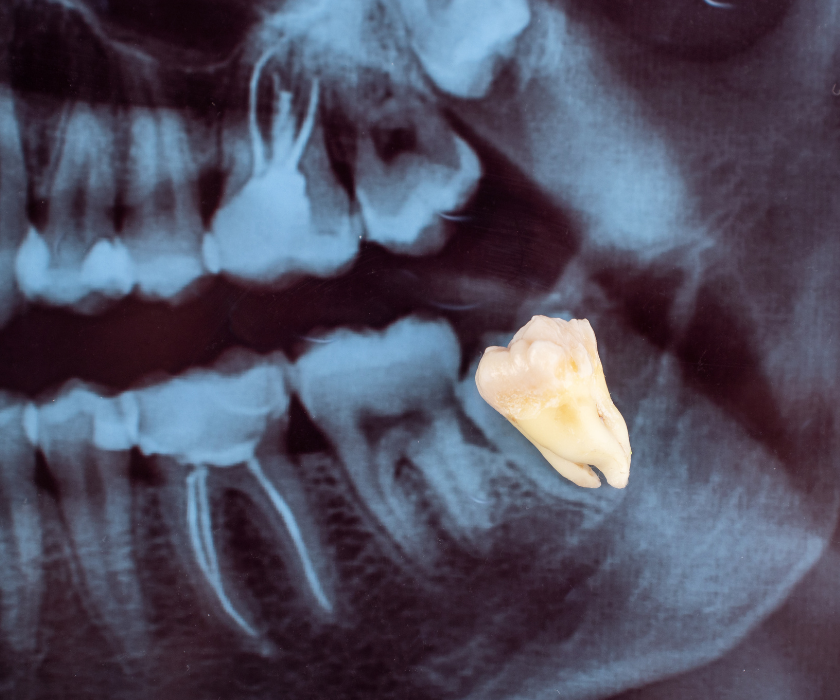

Răng khôn là chiếc răng mọc cuối cùng trên cung hàm, thường xuất hiện trong độ tuổi từ 17 đến 25. Vì là răng mọc sau cùng nên không còn đủ khoảng trống để phát triển thẳng hàng như các răng khác. Hệ quả là răng khôn rất dễ mọc lệch, mọc ngầm, đâm ngang sang răng kế cận, gây đau nhức và biến chứng viêm nhiễm.

Không phải tất cả các răng khôn đều cần nhổ, tuy nhiên trong đa số trường hợp – nhất là khi răng mọc lệch, mọc ngầm hoặc gây ảnh hưởng đến răng số 7 – việc can thiệp nhổ bỏ là điều cần thiết để ngăn ngừa hậu quả nghiêm trọng về sau.

Răng khôn là nỗi ám ảnh của nhiều người